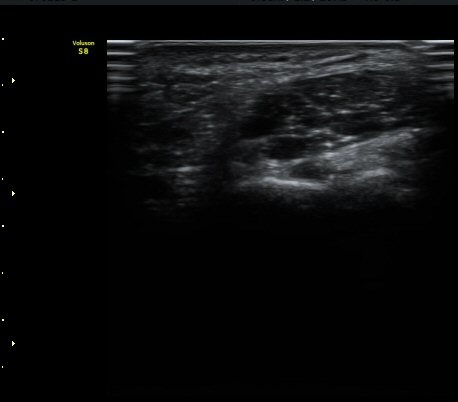

ŽÃËÀÚ¸¦ Á» ´õ ³»ÃøÀ¸·Î °æ»ç¸¦ ÁÖ¾î °¥°í¸®»À °í¸®ÀÇ Ãø¸éºÎ¸¦ °üÂûÇÏ´Ï °¥°í¸®»À °í¸®ÀÇ

ÇÇÁú°ñ ¿¬°á¼º ¼Ò½Ç(°ñÀý)°ú ±¹¼ÒÀû Àú¿¡ÄÚ ºÎÁ¾ÀÌ °üÂûµÇ°í Àú¿¡ÄÚ ºÎÁ¾ ¿ÜÃø¿¡¼­ ö°ñ½Å°æ

½ÉºÎ°¡Áö°¡ °üÂûµÈ´Ù(±×¸² 2, 3, 4,).